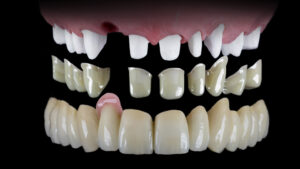

ケース3:インプラントを望まなかった40代女性

右上の奥歯を失い、保険義歯を使用していたが外れやすく人前で気になっていたとのこと。犬歯に引っかかる金属のクラスプも見えるのが嫌で、ほとんど外していたそうです。上顎をテレスコープ義歯にすることで外見と安定性が改善し、食事も会話も楽しめるようになりました。下顎は矯正やジルコニアによる修復も合わせて行い、全体の審美性も向上しました。

治療後は見た目が若返り、患者さん自身も非常に満足されていました。